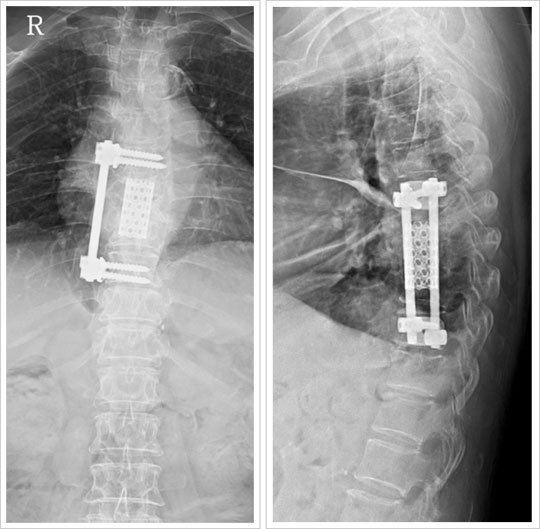

¢Á ÀåÁ¡ : º´º¯ÀÌ ÀÖ´Â ºÎÀ§¸¦ Á÷Á¢ Á¦°ÅÇÏ°í ½Å°æÀÇ ¾Ð¹ÚÀ» Ç®¾îÁÙ ¼ö ÀÖÀ¸¸ç, Àü¹æºÎ¸¦

ưưÇÏ°í °ß°íÇÑ Ã´Ã߸¦ À¯Áö½Ãų ¼ö ÀÖ½À´Ï´Ù.

¢Á ´ÜÁ¡ : ±ØÈ÷ µå¹°Áö¸¸ º¹ºÎ³ª ÈäºÎÀÇ ¿¹±âÄ¡ ¾ÊÀº ¼Õ»óÀÌ ÀÖÀ» ¼ö ÀÖ½À´Ï´Ù.